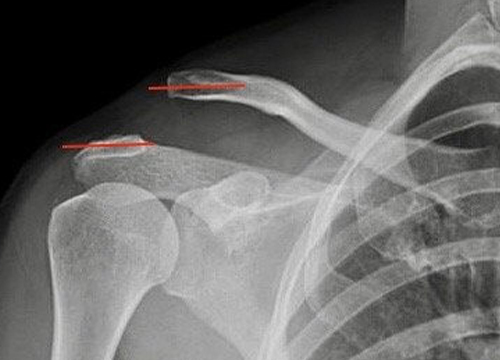

Luxação acrômio-clavicular

Ocorre frequentemente em traumatismos quando o paciente cai sobre o ombro. Comum em esportes como judô, ciclismo e futebol. A articulação entre a clavícula e o acrômio é estabilizada por dois conjuntos de ligamentos: um entre o acrômio e a clavícula e outro entre a clavícula e o processo coracoide. A luxação acromioclavicular pode ser […]